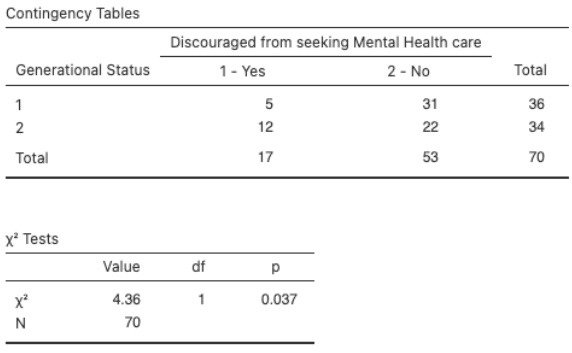

The Role of Generational Status in Access to Mental Health Care and Quality of Mental Health Among First and Second and Later-Generation Asian Indians in the U.S.

This study examines how generational status affects access to mental health care and quality of mental health among Asian Indians in the U.S.

Posted by buchanle on Tuesday, April 30th, 2024 in May 2024, Asian Indians, Generational Status, Mental health care, Mental health quality